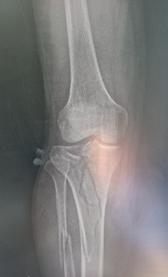

Schatzker III, Osteosinteză cu șuruburi percutană

Schatzker VI, Reducere sângerândă și osteosinteză cu 2 plăci

În baza examenului radiologic au fost propuse mai multe clasificări, dar cea mai folosită este cea a lui Schatzker:

Schatzker I: fracturi cu separare hemiplatou extern

Schatzker II: fracturi cu separare și înfundare hemiplatou extern

Schatzker III: fracturi cu înfundare hemiplatou extern

Schatzker IV: fracturi hemiplatou intern

Schatzker V: fracturi hemiplatou extern și intern

Schatzker VI: fracturi cu extensie metafizo-diafizară